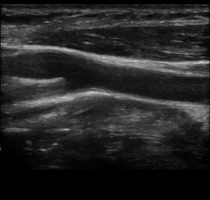

Im Praxisalltag steht zunächst die Erfassung der Beschwerdesymptomatik: schneller Pulsschlag, Herzstolpern, Leistungsmangel, Luftnot, Schmerzen in der Brust, Wassereinlagerung in den Beinen, Schwindel oder

Kollapsereignisse. Zu deren Abklärung werden technische Verfahren eingesetzt wie z.B. der Herzultraschall oder Belastungstests.